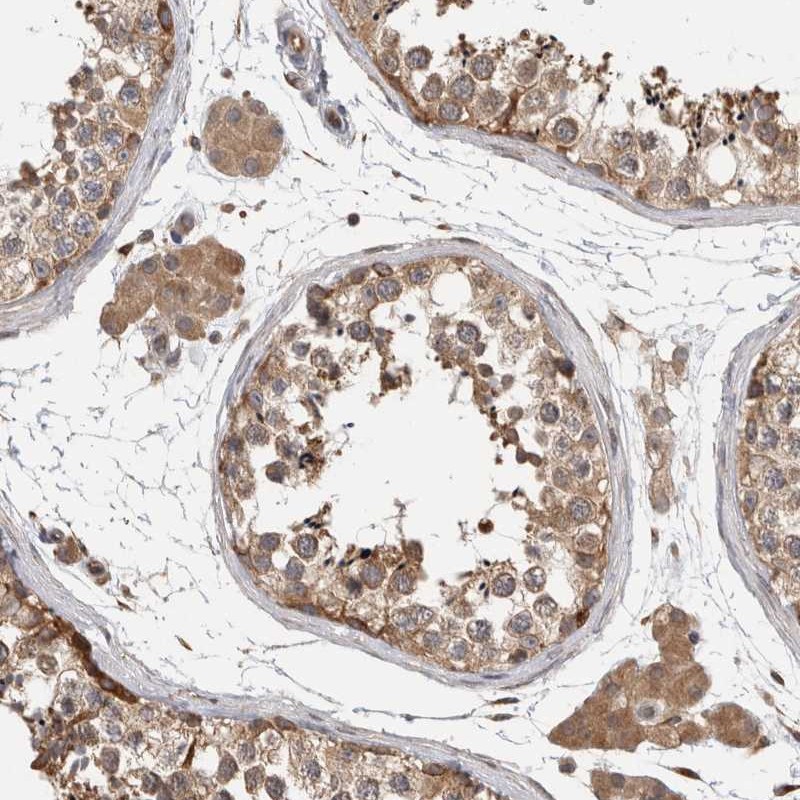

Immunohistochemical staining of human testis shows moderate cytoplasmic positivity in cells in seminiferous ducts and Leydig cells.